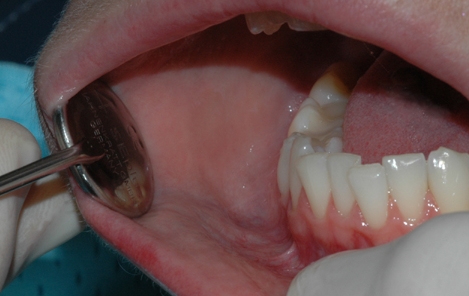

Tannkjøttet og tennenes benfeste blir vurdert